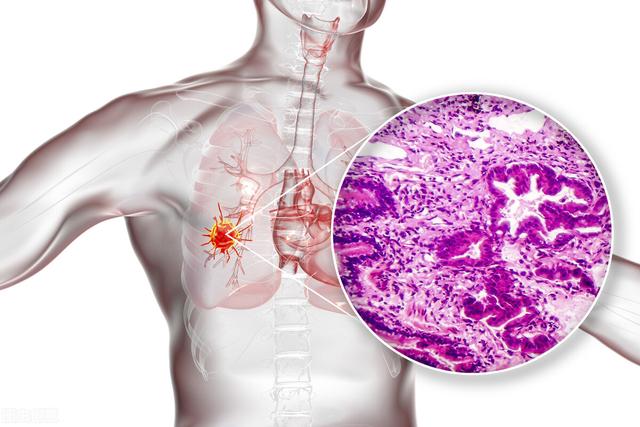

Lungenkrebs wird unterschieden in Adenokarzinom, Plattenepithelkarzinom, großzelliges Karzinom, kleinzelliges Karzinom, Karzinoidkarzinom usw. Wenn diese Krebsarten klein sind, sind sie nicht so typisch wie wenn sie groß sind.

Es handelt sich um einen Fall von chirurgisch bestätigtem Adenokarzinom der Lunge.

Kleine bösartige Knoten in der Lunge weisen oft typische Anzeichen von Bösartigkeit auf. Die Dichte innerhalb des Knotens ist oft ungleichmäßig, einige frühe Knoten werden glasig oder haben eine gemischte glasige Dichte, und in einigen der Knoten sind kleine Hohlräume zu sehen. Die Ränder sind noch typischer, da bösartige Knoten eine große Blutzufuhr für ihre Ernährung benötigen, so dass die Ränder oft mit kurzen Graten und kleinen Ansammlungen von Blutgefäßen, den so genannten vaskulären Clustern, infiltriert sind, die in unmittelbarer Nähe zu kleinen Gefäßen in kleinen Knoten zu sehen sind.